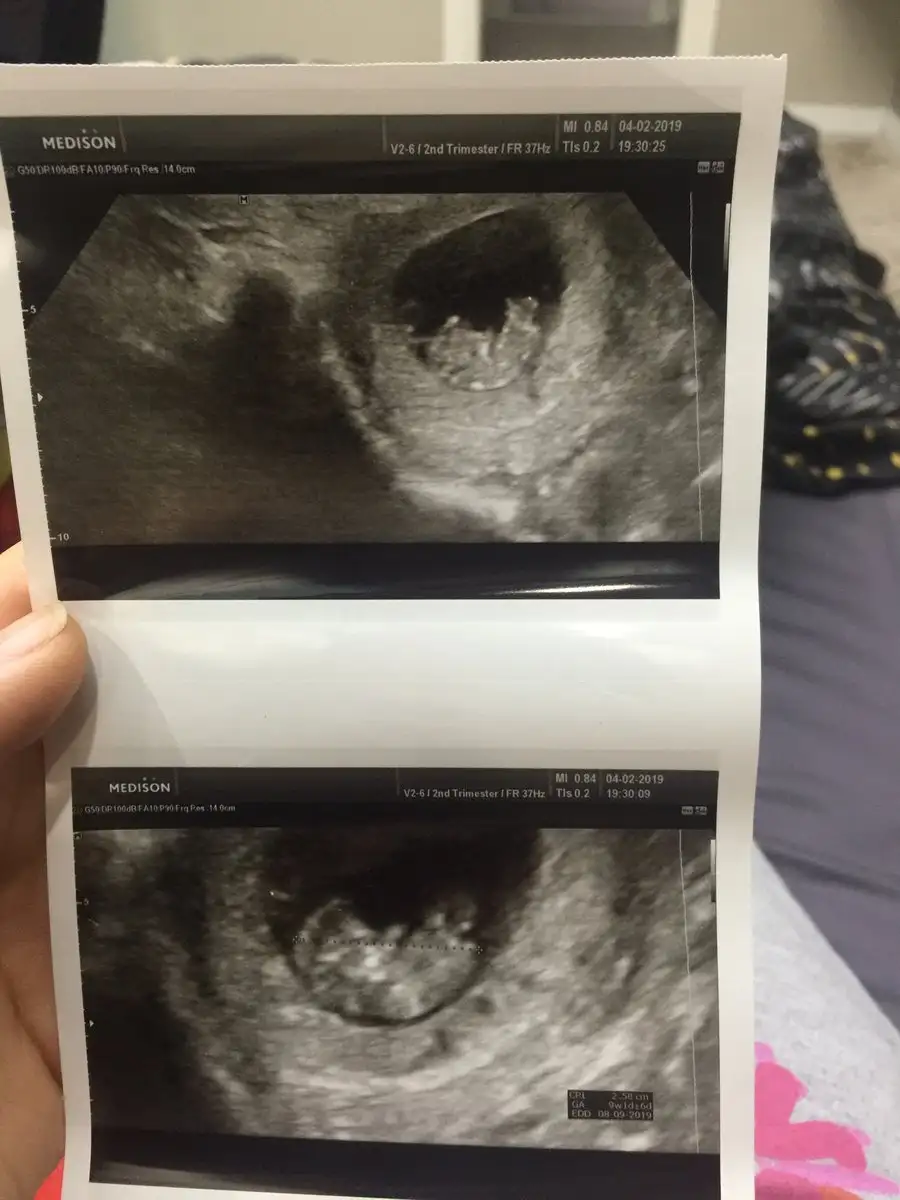

Merhaba; bir ultrason kağıdı 6 haftalık diğer ikili olan 9 haftalık resimler benim bebeğimin cinsiyeti tahminen sizce nedir arkadaşlar ?

Tecrübeli arkadaşlardan tahminler alabilirmiyim?